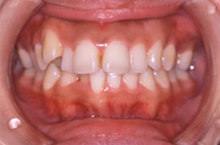

| 症状 | 前歯が出っ張ってものが噛み切れません。 歯並びの幅が狭くなり,下顎が後ろに押されています。 |

| 治療法 | スプリントセラピーを行った後、セラミックブラケットを用いて矯正治療を行った。 |

歯を抜いても歯並びが狭く小さくならないように治療します。

上顎の真ん中にあった骨隆起という、余分な力がかかるとできるでっぱりがなくなってきました。

歯並びの幅が広がって、きれいなU字型になってきました。これが本来の歯列の形です。